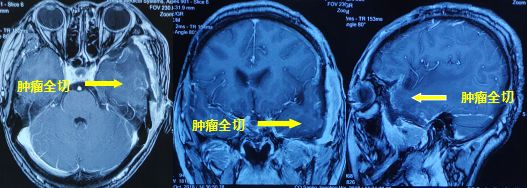

经过充分考虑,患者同意手术!由首都医科大学三博脑科医院专家、我院神经外科主任孙玉明主刀,彭俊副主任医师配合,在全麻下为患者进行左侧额颞入路左颞叶肿瘤切除术。

术后恢复较好,复查核磁提示肿瘤切除满意,水肿明显消除,中线基本回位。病检结果提示血管瘤型脑膜瘤,WHO Ⅰ级。